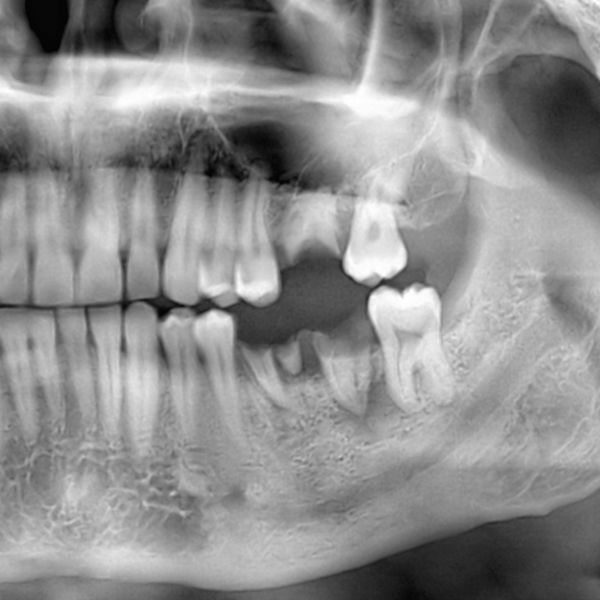

Dental Extractions and Bone Grafting

Helping our patients maintain strong, healthy teeth is of paramount importance, but there are instances a tooth is beyond restoration and may need to be extracted. Sedation dentistry, including nitrous oxide and oral sedation, can be used to minimize discomfort, and our gentle techniques ensure the procedure will be nearly painless. Patients may also choose to undergo bone grafting immediately after - a procedure known as socket preservation - to guard against the natural bone loss process, and prepare the treatment site to receive an implant in the future.